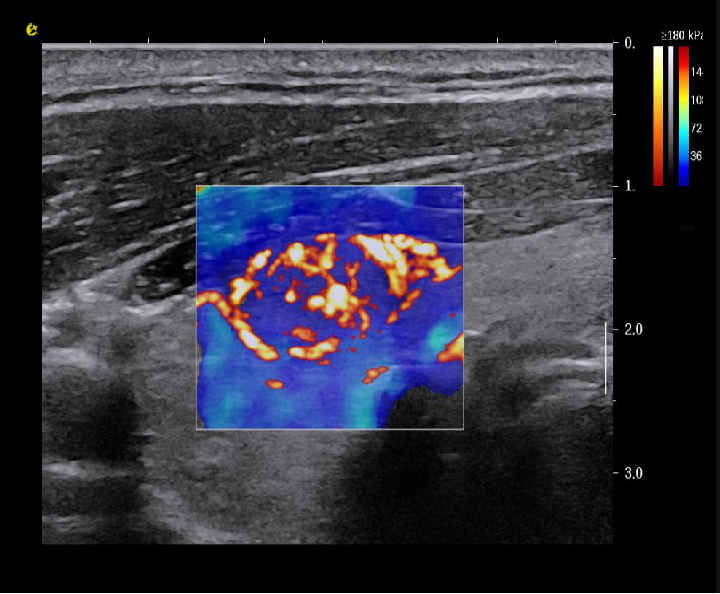

平面波超微细血流显像

能够提供更多真实的组织细小及末梢血管的血流信息,直观的观察组织内部的血管架构及血流形态的情况,提供临床更多有价值的诊断信息。

临床应用:

肿瘤鉴别诊断(肝脏、肾脏、甲状腺、乳腺、  涎腺等)

淋巴结评价(炎症、肿瘤)

肌骨系统临床诊断和疗效监测(关节、滑膜、韧带、肌肉炎症、 损伤等)

斑块内新生血管评估

超声介入术前进针方案提供血流参考信息

超声介入术后疗效评估

image.png